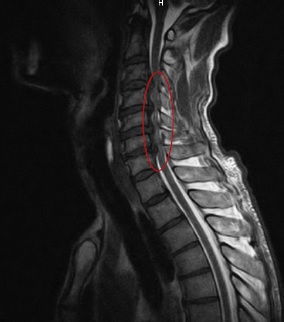

Los estudios imagenológicos con resonancia magnética de la región cervical (Figura 2) demostraron hernias discales C3-C4, C4-C5, C5-C6, con gran compresión de la pared anterior de la médula espinal, observándose alteraciones de la intensidad de la señal de la misma. Rectificación de la lordosis cervical con marcados cambios degenerativos, lo cual fue compatible con mielopatía espondilótica cervical.

Los resultados de los estudios neurofisiológicos este caso confinaron las alteraciones a un segmento definido del sistema nervioso, con afectación tanto motora como sensitiva, poniendo en duda el diagnóstico de ELA. Las imágenes de resonancia magnética confirmaron los signos de espondilosis cervical marcada con cuatro grandes hernias discales, que provocaban gran compresión de la médula espinal cervical, tanto de su cordón anterior y motor, como del posterior y sensitivo, lo cual explicó la sintomatología presentada por el paciente.